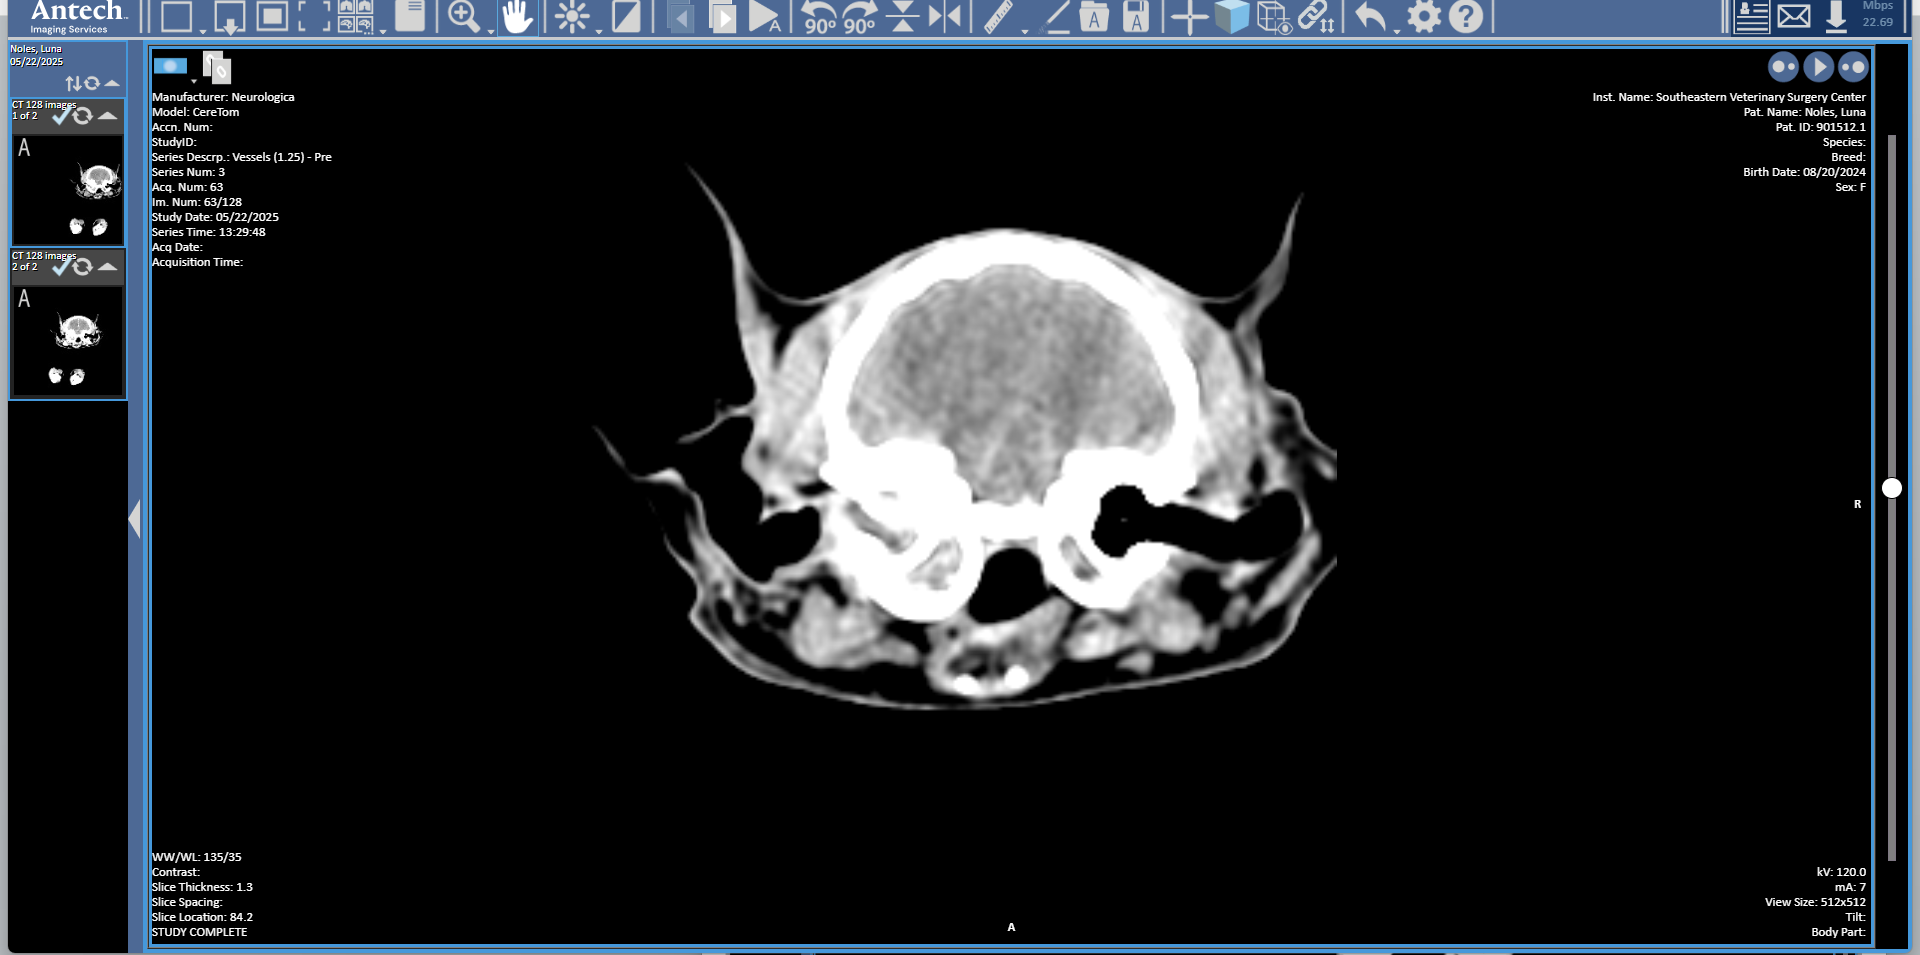

Luna is a 1 yr old Spayed Maine Coon who presented to SEVSC for an inflammatory polyp of the left middle ear extending into the external ear canal. The polyp was successfully removed via a ventral bulla osteotomy.